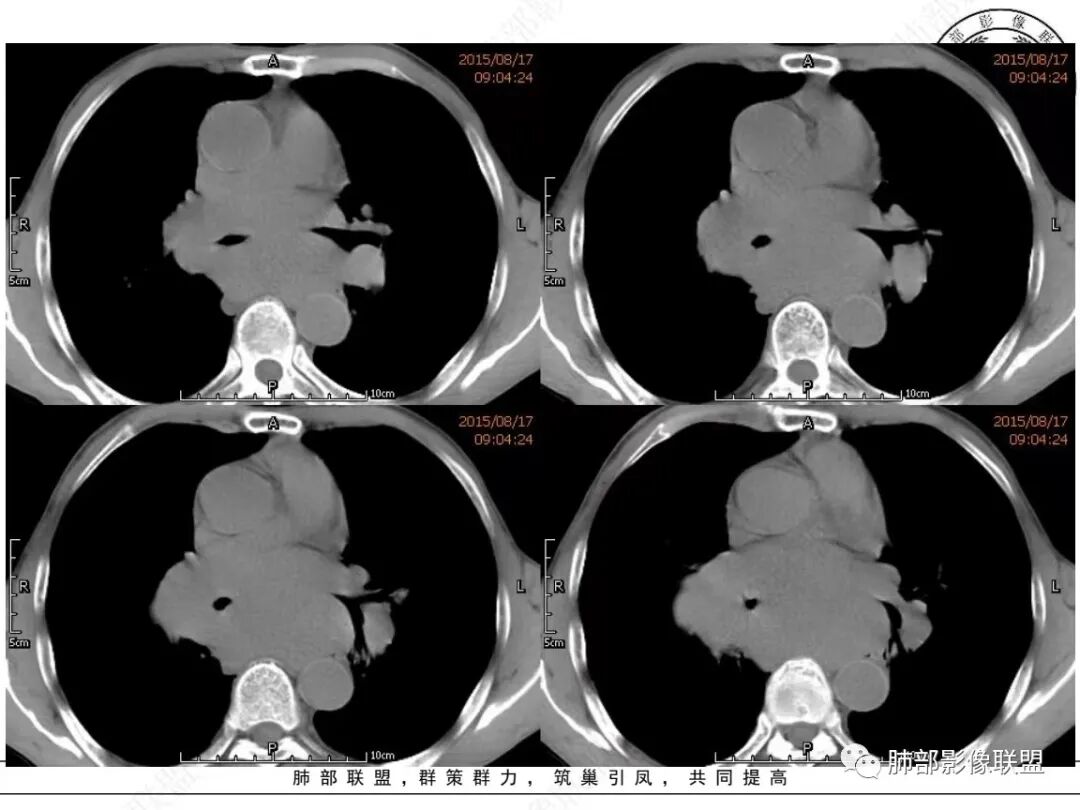

老年男性,右侧肺门可见团块状占位包绕气管,气管受压变窄,纵隔见巨大团块状占位,另纵隔可见肿大淋巴结,增强肺门及纵隔肿块强化不明显,内部可见血管影,周围结构只是受压移位,另颌下淋巴结穿刺慢性淋巴结炎,首先考虑小细胞癌,鉴别淋巴瘤、结节病。

右肺下叶小结节,右肺门及中后纵膈淋巴结肿大融合,强化均匀,主支气管、中间段及下叶支气管受压变窄,右下肺静脉受压变窄,考虑小细胞癌,鉴别淋巴瘤

老年男性,纵隔及肺门多发肿大淋巴结,相互融合呈团块状,包绕支气管官腔,呈针尖样狭窄,增强后轻度强化,考虑小细胞肺癌

纵隔及肺门淋巴结肿大相互融合呈冰冻纵膈,支气管受压变窄呈针孔样,老年男性吸烟患者,考虑小细胞肺癌。

老年男性,有吸烟史,双颈部肿块,双肺纵隔淋巴结多发淋巴结肿大并融合成块,气管及右肺下叶支气管受压狭窄,考虑恶性,淋巴瘤可能,鉴别小细胞肺癌。

老年男性,有吸烟史,右肺下叶背段示小结节,纵隔、腋窝及右肺门淋巴结节肿大,气管受压狭窄,后纵隔软组织内示血管走行,考虑小细胞>淋巴瘤。

晨读老年男性,长期吸烟。右肺门、纵隔多发肿大淋巴结、融合成团块,中间支气管、右肺下叶支气管受压变窄,增强扫描强化程度较轻,血管包埋。另两侧腋窝亦见多发肿大淋巴结。常规恶性没问题,小细胞?淋巴瘤?但是於老师的病例总感觉没那么简单。

纵隔内中后纵隔及右肺门淋巴结肿大,形成大肿块,整体密度均匀,并轻度强化,见“血管飘浮”征,包绕气管分叉及右主支气管及中间段支气管明显受压狭窄,并包埋右肺门血管束,无侵蚀破坏,右肺动脉后壁见压迹影,右肺下叶背段有阻塞性炎症,首选淋巴瘤,支气管超声内镜活检,明确诊断!

MCL的CT表现为分布无规律的全身多区域淋巴结受侵,少有单一区域淋巴结受累,结外器官受侵多见;MCL有一般NHL淋巴结受累基本CT表现,平扫CT表现为病变密度均匀,受累淋巴结区内呈融合状生长,边界清楚,增强后病灶呈均匀、中等强化,一般病变内无低密度坏死区。确诊需要病理及免疫组化,根据肿瘤组织形态学和免疫组织化学 CD5 及cyclin D1 的表达绝大多数 MCL 可做出明确病理诊。

1.小细胞肺CA:好发吸烟老年男性。常有血液NSE及胃泌素释放肽前体升高。Syn、CgA、CD56阳性。其CT特点可有:冰冻纵隔、冰冻肺门。血管包埋征。针尖样支气管。鸭蹼状凸起。娘小崽大。脂肪间隙消失(常指纵隔及肺门内)。阻塞性炎症不重。侵袭性强。破坏力不强。收缩力弱,内无空泡。沼泽样强化,坏死散而小,坏死不彻底,强化偏低。表面圆钝,角状及条状凸起,蠕虫样表现,腊肠样尾巴(朝肺门侧或背离肺门侧均可以)。胸水多“清澈”(可以理解为淋巴液回流障碍导致的胸水)。点簇状钙化(类似盐与胡椒样)。多见癌性淋巴管炎。另外黄勇老师提出胸膜下的小细胞肺癌具有“山丘征”的特点。